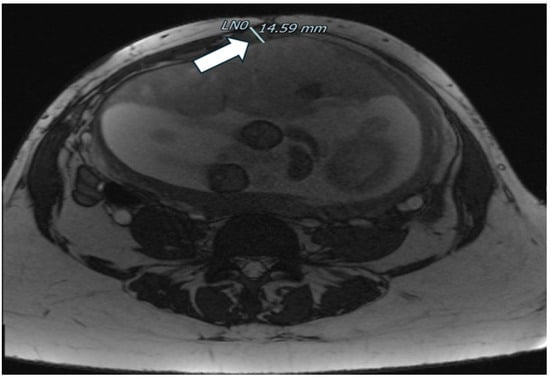

| Zermano S. et al. | 2024 | Yes | Yes | Yes | 24 5/7 | ||

| Zermano S. et al. | 2024 | 29 1/7 | No | Yes | Yes | Yes | |